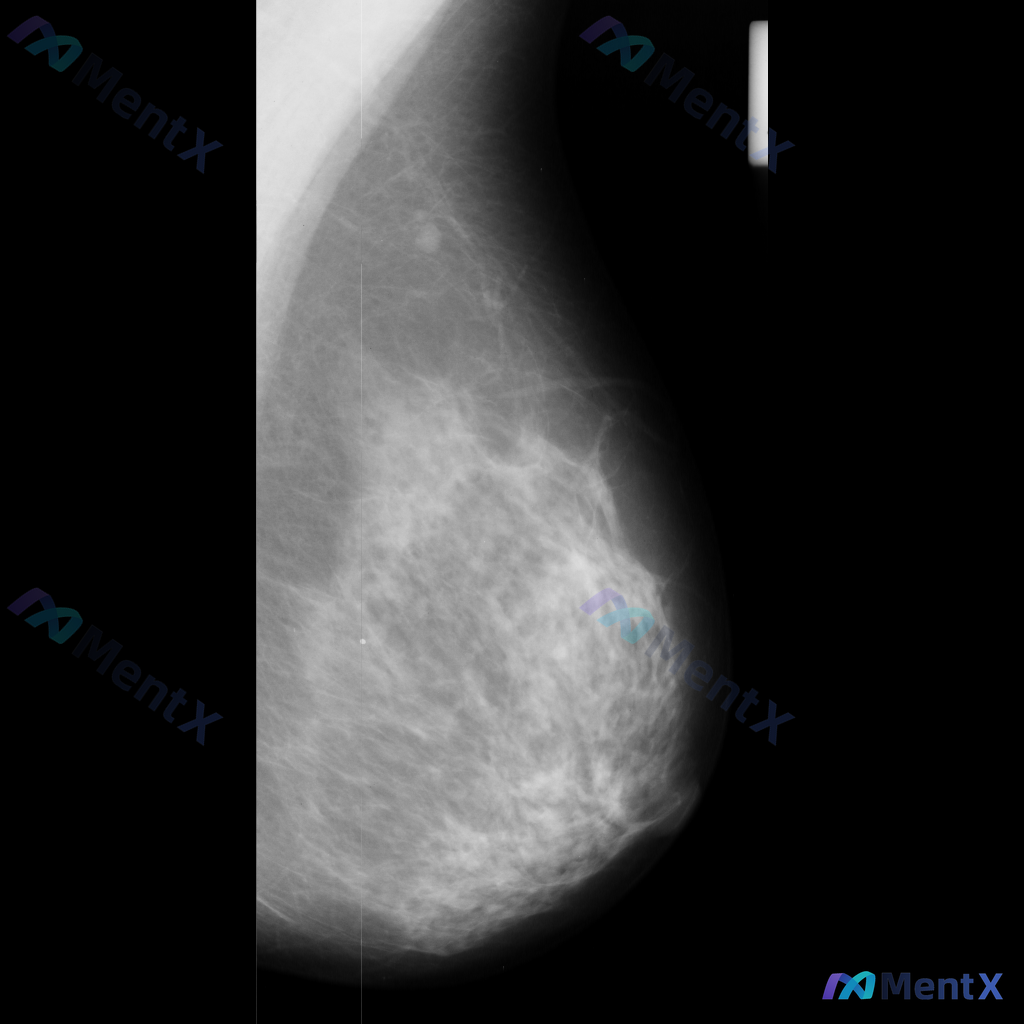

各位老师好,这里有一张乳腺钼靶影像(image: mdb281.png),影像中可见一些异常表现,想请大家一起讨论一下。

整理到一张单侧乳腺钼靶影像的读片资料,目前是单一体位图像,没有双侧对比。 影像表现整理 - 乳腺组织密度较高,属于多量腺体型或致密型背景 - 可见散在的钙化灶:图像中部偏下有数个点状或粗大钙化,形态不规则,但无典型恶性钙化的细小多形性、线样或分支状表现 - 乳腺下象限可见多个高密度圆形/卵圆形影,边...

整理了一份乳腺影像的读片资料,想和大家讨论下判断方向: 基本影像信息 - 单侧乳腺X光片,投照体位考虑可能为内外斜位(MLO) - 乳腺组织构成:不均匀致密型 - 影像质量:曝光适中,清晰度良好,无明显伪影 - 可见结构:皮肤、皮下脂肪层、乳头乳晕、Cooper韧带显示尚可;未见明确钙化血管或腋窝淋...

整理到一张左乳内外斜位(MLO)的钼靶影像资料,先和大家讨论一下读片的情况。 目前已知的信息: - 仅提供了左乳的MLO位单张投照影像 - 影像质量基本良好,基本结构可辨 - 后续补充说明提到患者的乳腺构成类型为不均匀致密型(BI-RADS C) 目前暂时没有更多临床病史、对侧乳腺影像或头足位(CC...